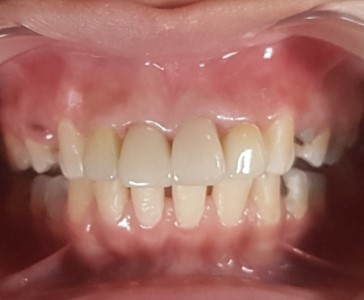

Before & After Gallery

Full E-MAX 4 crowns restoration